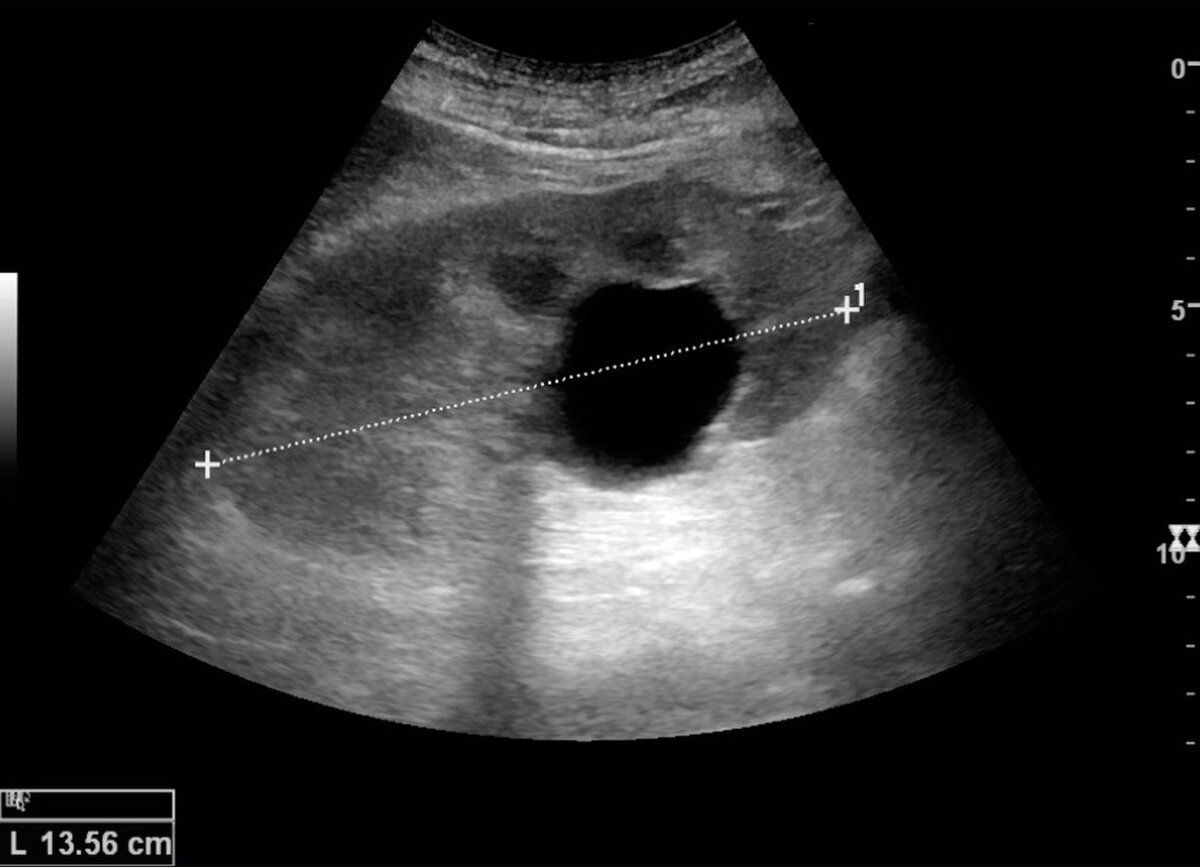

1 Больше всех поглощают ультразвук ( самые черные на изображении)

Это полости заполненные жидкостью ( сосуды, кисты, наполненный мочевой пузырь), они будут выглядеть на снимках как полностью или практически полностью черные структуры